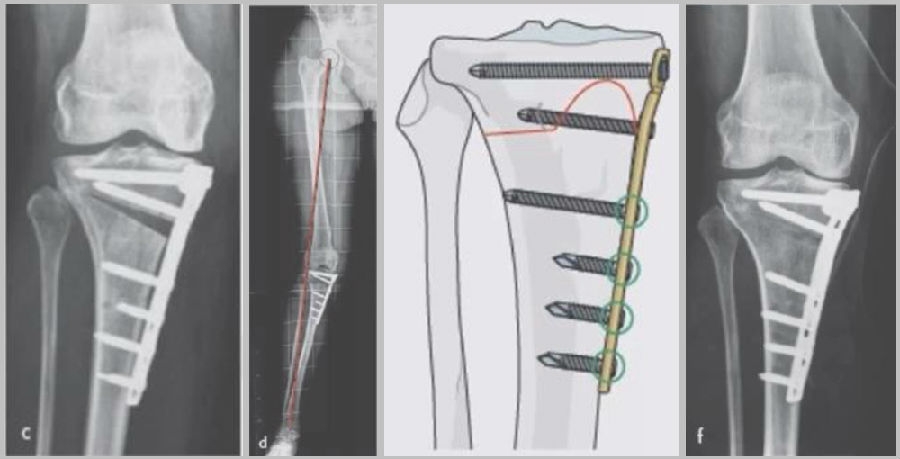

(2)Ⅱ型骨折

当出现Ⅱ型骨折时要特别注意,因为此时截骨的远端就是骨折的远端,近端只有上胫腓周围骨筋膜存在,所以相对来说Ⅱ型骨折并不稳定。

首先用拉力螺钉复位,调整好力线。然后做结构性植骨,延迟负重,所谓延迟负重就是延迟到外侧合页和上行截骨线处达到初始愈合,然后再让患者进行负重。如果不做结构植骨加延迟负重,就会出现一些非常严重的现象,如不愈合。

拉力钉复位,结构性植骨

左侧患者未植骨正常负重,术后4个月不愈合;右侧患者非结构性植骨过早负重,术后1年未愈合